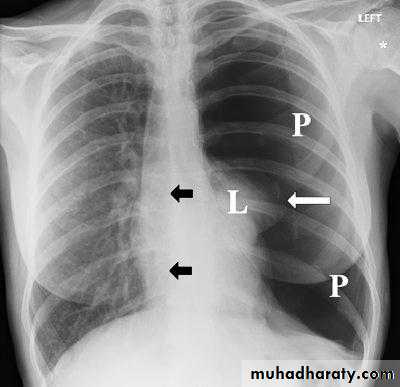

This frontal CXR reveals complete collapse ofthe right lung due to a massive right pneumothorax, which is also shiftingthe heart and other mediastinal structures to the left, (a tension pneumothorax).